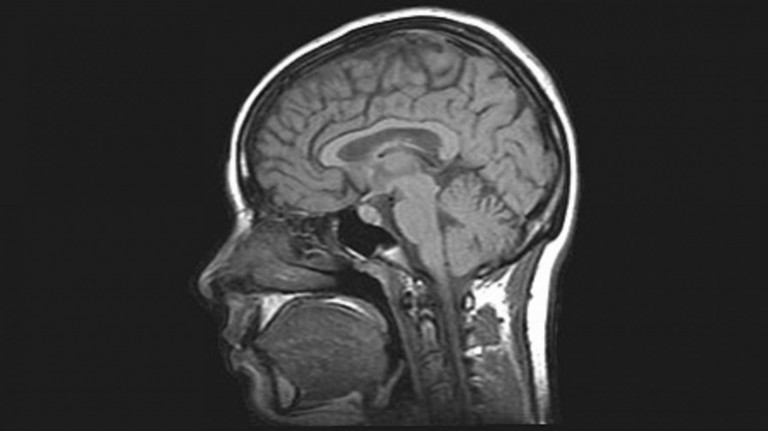

Νέα τεχνολογία που μεταφέρει DNA στον εγκέφαλο για να δημιουργήσει ο ίδιος μηχανισμό κατά της φλεγμονής μετά από τραυματισμό ανέπτυξαν επιστήμονες σε ποντίκια. Θα ακολουθήσουν κλινικές μελέτες σε ανθρώπους